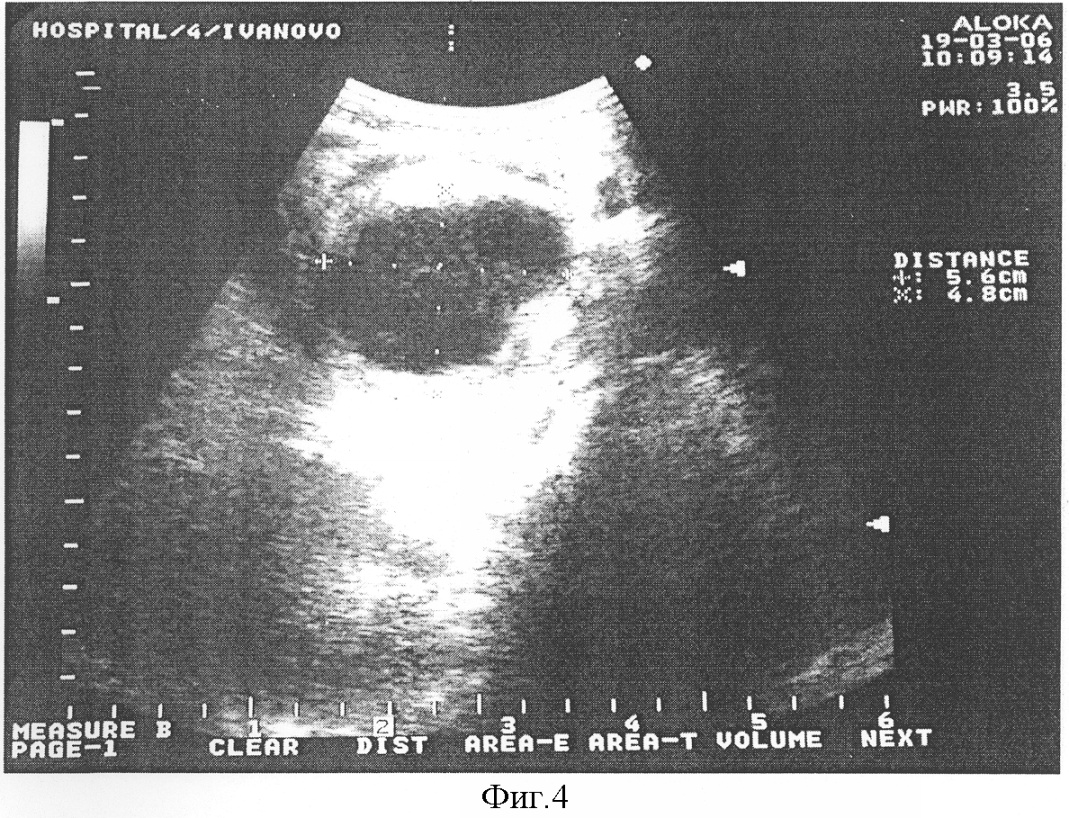

Пример. Больной К., 55 лет, И/Б № 1695, поступил в клинику 19.03.2006 года с жалобами на боли в верхней половине живота, частую рвоту, снижение массы тела. При рентгеноскопии желудка и двенадцатиперстной кишки выявлена компрессия нисходящей части двенадцатиперстной кишки за счет увеличенной головки поджелудочной железы (фиг.3). При выполнении УЗИ диагностировано полостное образование в проекции головки поджелудочной железы размерами 5,6×4,8 см (фиг.4). В плановом порядке 26.03.2006 г. произведена операция – наложение V-образного цистодуоденоанастомоза. В послеоперационном периоде на контрольной эхограмме 06.04.2006 в области головки поджелудочной железы (на месте псевдокисты) определяется образование размерами 3,0×3,1 см без полостного компонента (фиг.5). Пациент выписан в удовлетворительном состоянии, проходимость двенадцатиперстной кишки восстановлена, полость панкреатической псевдокисты не визуализируется.